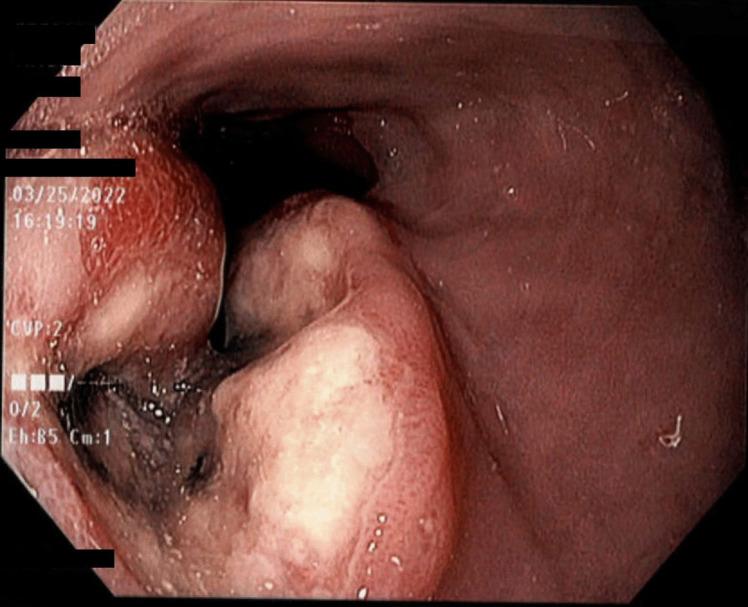

Case 1 is a 49-year-old female with abdominal pain and dysphagia and esophagogastroduodenoscopy (EGD) showing a friable mass at the gastroesophageal (GE) junction. Biopsies showed a poorly differentiated neoplasm and immunohistochemistry showed loss for SMARCA4. With metastatic disease, she agreed to undergo palliative chemotherapy and radiation, passing away at 4 months. Case 2 is an 88-year-old male with dysphagia, nausea, vomiting, and distal esophageal mass with biopsy showing a malignancy with loss of SMARCA4 expression. Due to extensive metastases, he was counseled on hospice care. Case 3 is a 53-year-old male with extensive alcohol and smoking history presenting with hematemesis, passing away shortly. Posthumous histopathology consistent with undifferentiated SMARCA4-deficient carcinoma of the esophagus. Results of the literature review indicate a predilection towards males (75.0%) and a variable age range (39-88 years). Majority (76.2%) reported with a distal esophagus location. Metastatic disease was common at initial presentation. Median survival was 2.60 months. Some were managed with chemotherapy and radiation.

病例 1 为 49 岁女性,有腹痛和吞咽困难,食管胃十二指肠镜(EGD)显示胃食管(GE)交界处有易碎肿块。活检显示为低分化肿瘤,免疫组化显示 SMARCA4 缺失。由于转移性疾病,她同意接受姑息性化疗和放疗,4 个月后去世。病例 2 为 88 岁男性,有吞咽困难、恶心、呕吐和远端食管肿块,活检显示为恶性肿瘤,SMARCA4 表达缺失。由于广泛转移,他接受了临终关怀咨询。病例 3 为 53 岁男性,有大量饮酒和吸烟史,表现为呕血,不久后去世。死后组织病理学检查符合未分化 SMARCA4 缺陷型食管癌。文献复习结果表明,男性(75.0%)和年龄范围(39-88 岁)均存在倾向性。大多数(76.2%)报告位于远端食管。初诊时转移性疾病常见。中位生存期为 2.60 个月。一些患者接受了化疗和放疗。